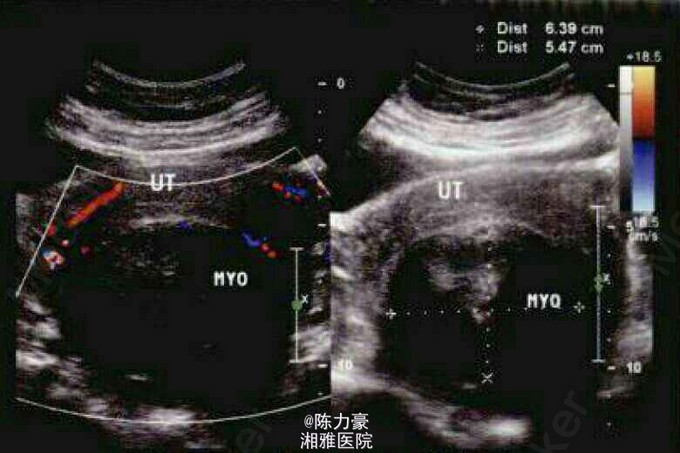

查体: 体温36°C,脉搏72/min,血压130/90mmHg。妇科检查:宫颈糜烂I度,见宫颈腺囊肿,子宫增大如妊娠5个月,耻骨联合后方为囊性感,活动受限,双侧附件未见异常。 辅助检查:B超提示:子宫平滑肌瘤。

初步诊断:① 子宫平滑肌瘤(恶变待排);②慢性宫颈炎。 静脉全麻下经腹部手术:子宫前位增大如妊娠5个月,质软,双侧附件未见异常,行全子宫切除术。 术中10号丝线缝扎子宫动静脉,7号丝线加缝,切开阴道前穹窿沿宫颈环切一周,阴道断端有数处小动脉出血,以2号肠线间断缝合数针,小动脉均以7号丝线缝扎止血,以4号丝线连续缝合盆壁腹膜。病理报告:子宫肌层平滑肌瘤(富于细胞性)。术后第7天给予伤口拆线,患者恢复良好。术后第12天在患者阴道左侧上端可扪及如鸡蛋大小的包块,略有囊性感。考虑血肿可能性大,炎性包块待排。行超声检查提示:(左)阴道上端3cm囊性包块。术后第13天给予口服中药活血化瘀治疗。请理疗科会诊, 处理意见:短波理疗。术后第14天,患者盆腔包块比昨日有所增大,阴道少许出血,考虑血肿可能性大,因理疗热效应使血肿增大,故停理疗。并给口服维生素C及注射酚磺乙胺,继续服中药治疗。术后18d盆腔包块比前有所缩小,压痛不明显,继续服中药治疗。术后22d盆腔包块略缩小,患者于当日出院,院外服中药治疗,及时复査。